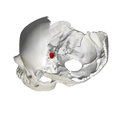

Hypophysial fossa shown in red. Sphenoid bone seen from above. Sella turcica shown in red.

Sphenoid bone seen from above. Sella turcica shown in red. Base of skull - Sella turcica, tuberculum sellae and hypophyseal fossa